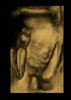

Dziewczyny chce Wam się pochwalić moją còreczką. Dziś byłam na wizycie i gin potwierdził płeć. Mała waży już 170 g. Jest wszystko w porządku z ciąża, tylko dostałam żelazo, bo mam niski hemakrotyt i limfocycty... Za miesiąc kontrola. Maleństwo wszystkie witaminki mi zabiera heheh